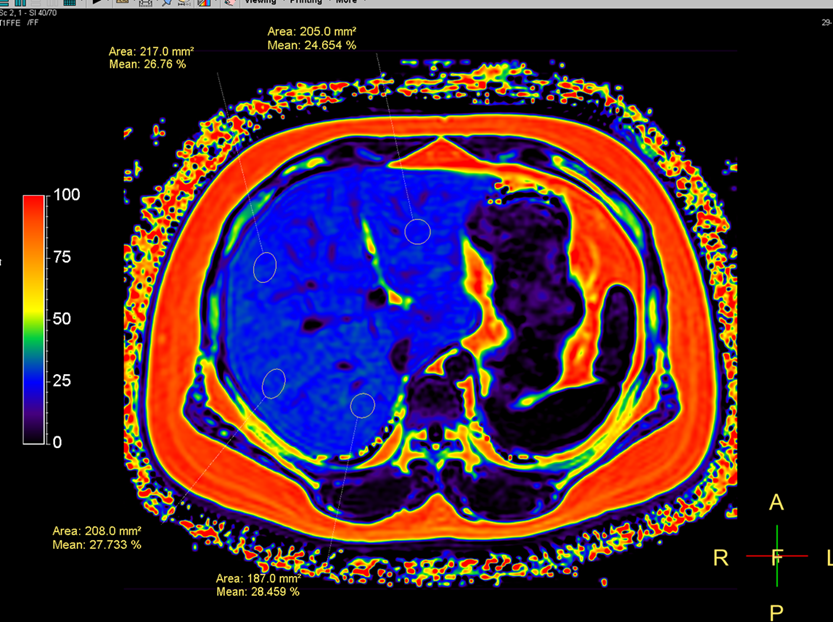

「磁共振脂肪定量基于磁共振成像技术,通过测量肝脏中水分子和脂肪分子的质子密度,来精确地分析出肝脏的脂肪含量,可以为临床诊断和治疗提供支持。」刘强主任介绍,它的扫描范围包括整个肝脏,扫描时间仅 14 秒, 一次扫描可得到同相位、反相位、水相、脂肪相、T2*、R2*六组图像。通过计算机处理可以得到 PDFF 图,从而测量对应肝脏的脂肪含量。

从脂肪分数图(伪彩图),可直观展示脂肪含量分布,皮下脂肪及腹腔脂肪呈红色,正常肝实质为浅蓝色,随着肝脏脂肪含量的增高,逐渐由浅蓝色变为深蓝色。